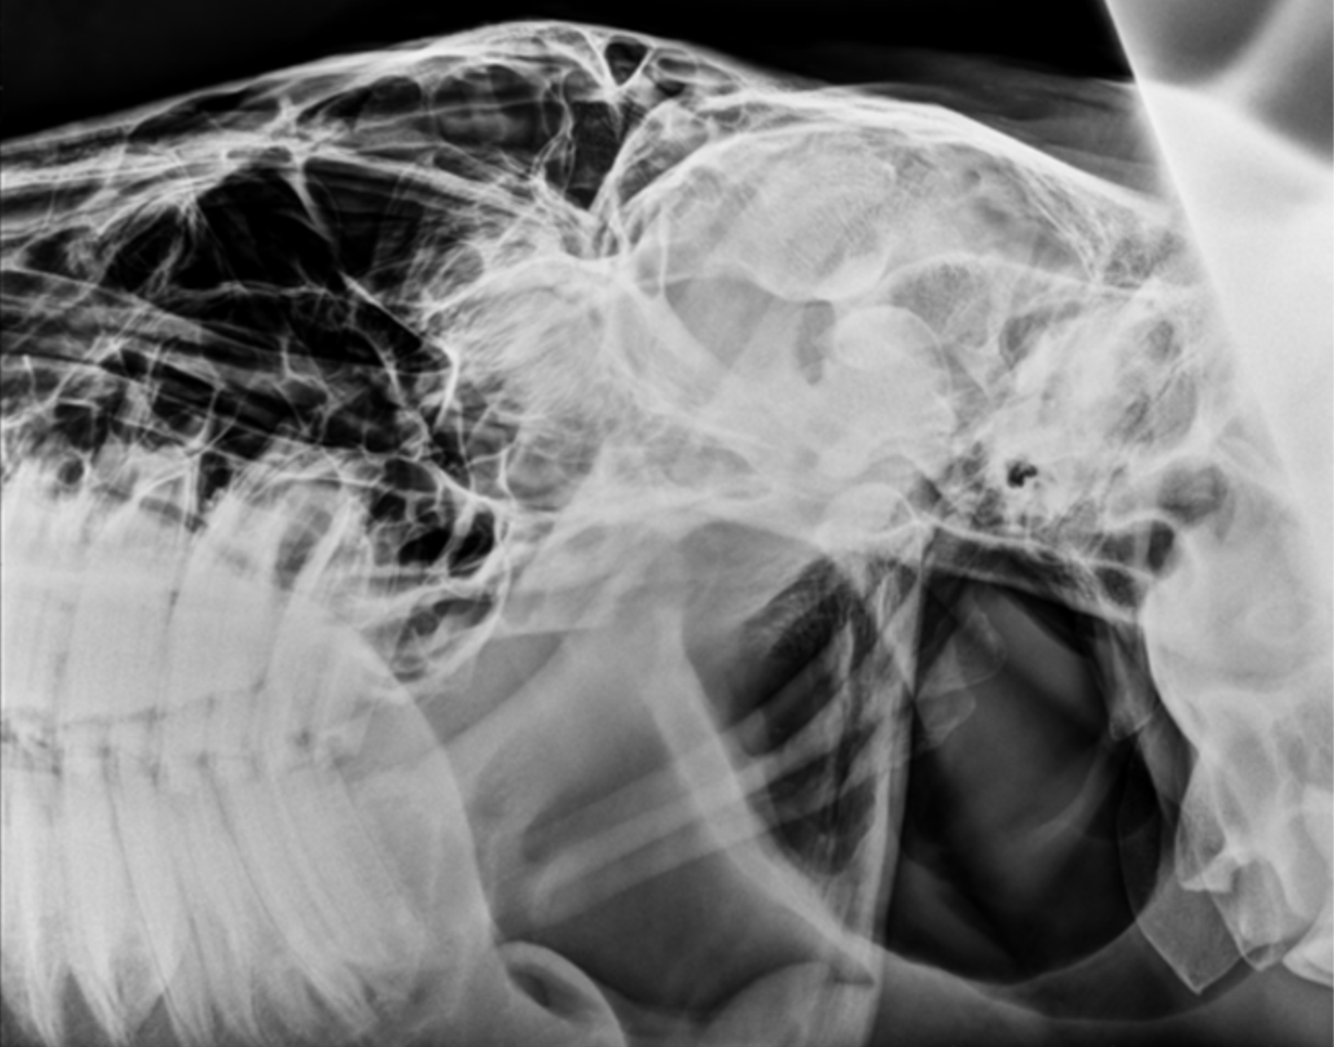

left lateral equine skull

orange: gutteral pouches (left and right)

yellow: pharynx

blue: ethmotrubinates

red: mandibles (left and right)

white: epiglottis

dark blue: styelohyoid bones (left and right)

green: basiphenoid